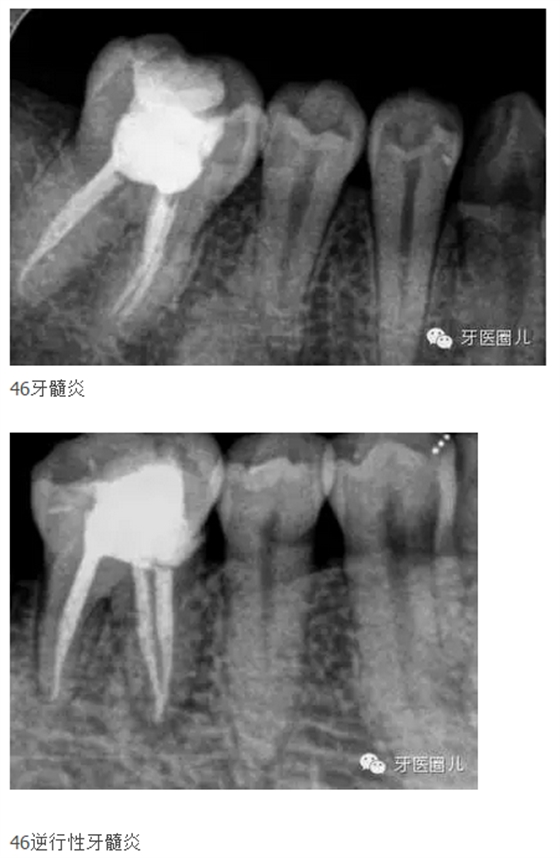

38,因為3637缺失需要作為基牙

這三個病例采用protaper器械,最后一個病例有不足,遠(yuǎn)中舌根根尖2mm有一個嚴(yán)重的向上彎曲,預(yù)備和充填時沒有到達(dá),術(shù)前評估和術(shù)中評估時覺得這個病例難度超過了我的操作范圍,但是患者沒有精力選擇更好的醫(yī)院,我于是和他講明狀況盡量做到我能做的了